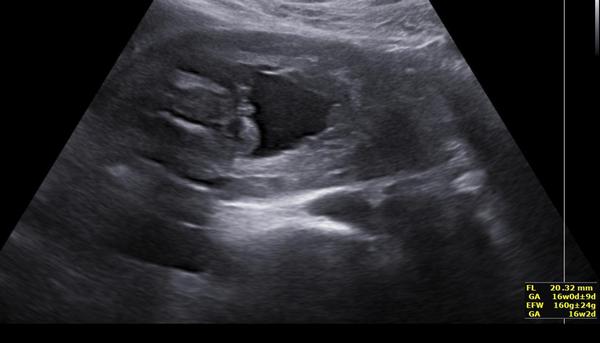

dnes jsem byla na těhotenské kontrole (16+5) a kontrolu prováděla asistentka, která zatím není tolik zkušená a netroufla si určit pohlaví dle utz. Samozřejmě na finálnější úsudek si počkám na velký ultrazvuk ve 20. tt, ale jsem zkrátka nedočkavá a chtěla bych se zeptat, zda Vaše zkušenější oko ze snímku náhodou pohlaví nepozná.

bohužel z přiloženého snímku to posoudit nelze 🙂 , nezbývá tedy než vyčkat...